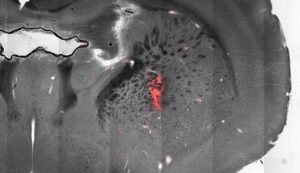

Buffalo Üniversitesi’nden bilim insanları farelerin beynine manyetik folyolar yerleştirerek, fiziksel hareketlerini kontrol etmeyi başardı. Araştırmacılar farelerin beyninde koşma,dönme ve durmaya